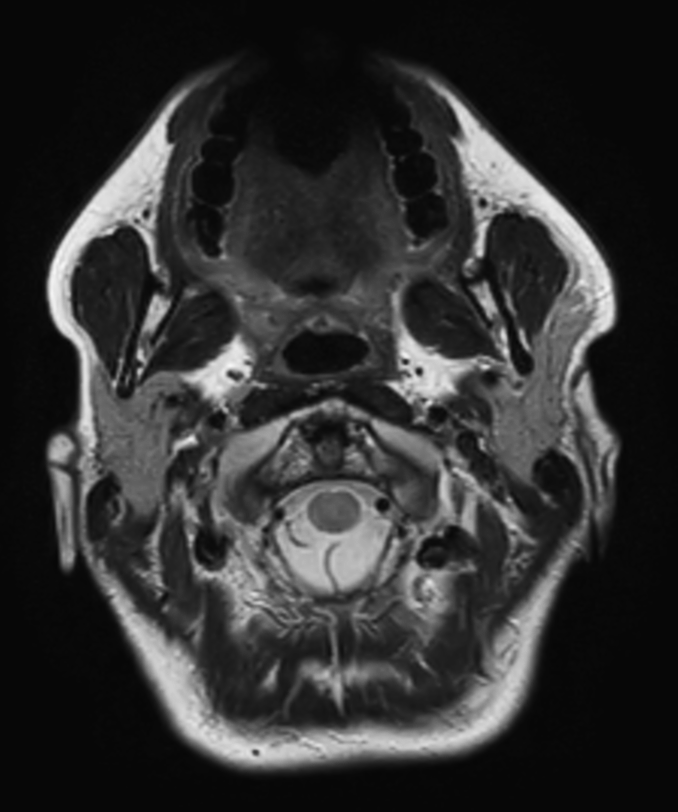

Axial T2w  mDIXON TSE (In Phase)